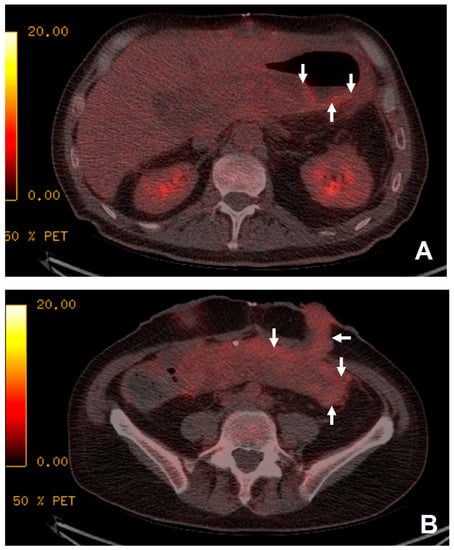

Figure 3. The patient presented with continued pyrexia and a white cell count of 40 × 109cells/L. CT from 4 days prior demonstrated a lesser sac collection (A) with clinical concerns that the lesser sac collection (white arrows, image (A)) may be the source of sepsis and the permacol gusset mesh used for closure may be infected. 18F-FDG PET/CT (B,C) demonstrated the collection in the lesser sac (white arrows, image (B)) is likely to be innocuous as it did not show high tracer uptake and there was no significant uptake at the site of the permacol gusset closure material (short arrows, image (C)) to suggest an infected implant. The patient avoided a repeat operation for a surgical washout of the lesser sac collection and the removal of the closure mesh.